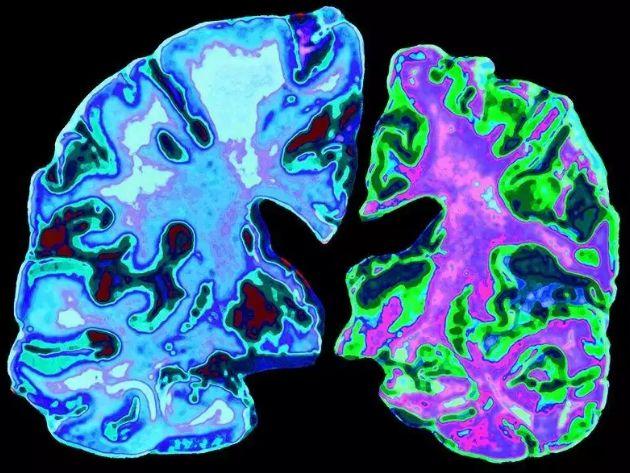

与 70 岁的正常大脑(左)相比,70 岁阿尔茨海默病患者的大脑切片 图片来源:Jessica

通过多年研究,目前人类已知AD患者的典型特征是脑萎缩。

在显微镜下,病患大脑中的β淀粉样斑块和神经纤维缠结清晰可见,其中神经纤维结是由Tau蛋白质过度磷酸化并且堆积在细胞内聚集而成。